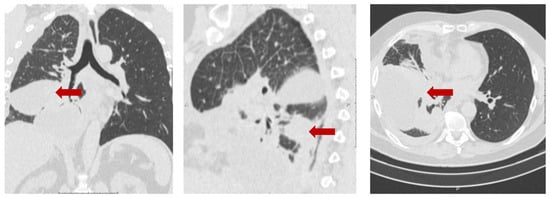

3.6.1. A Clinical Example Demonstrating a Favorable Outcome of the Disease and the Evolution of the Number of CTCs Detected in the Peripheral Blood